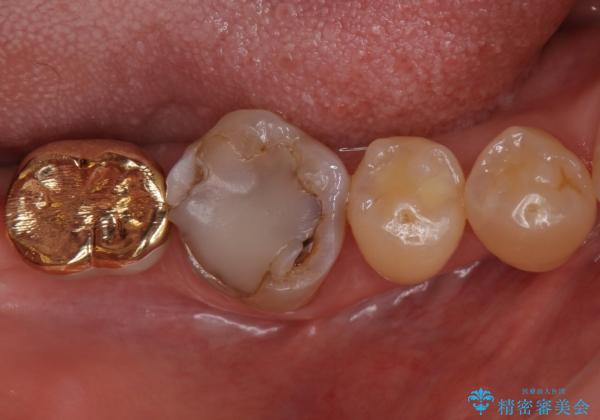

不適合だった詰め物の裏側に大きな虫歯がありました。

セラミックインレーやアンレーでは強度に不安が残るため、クラウンでの修復処置としました。